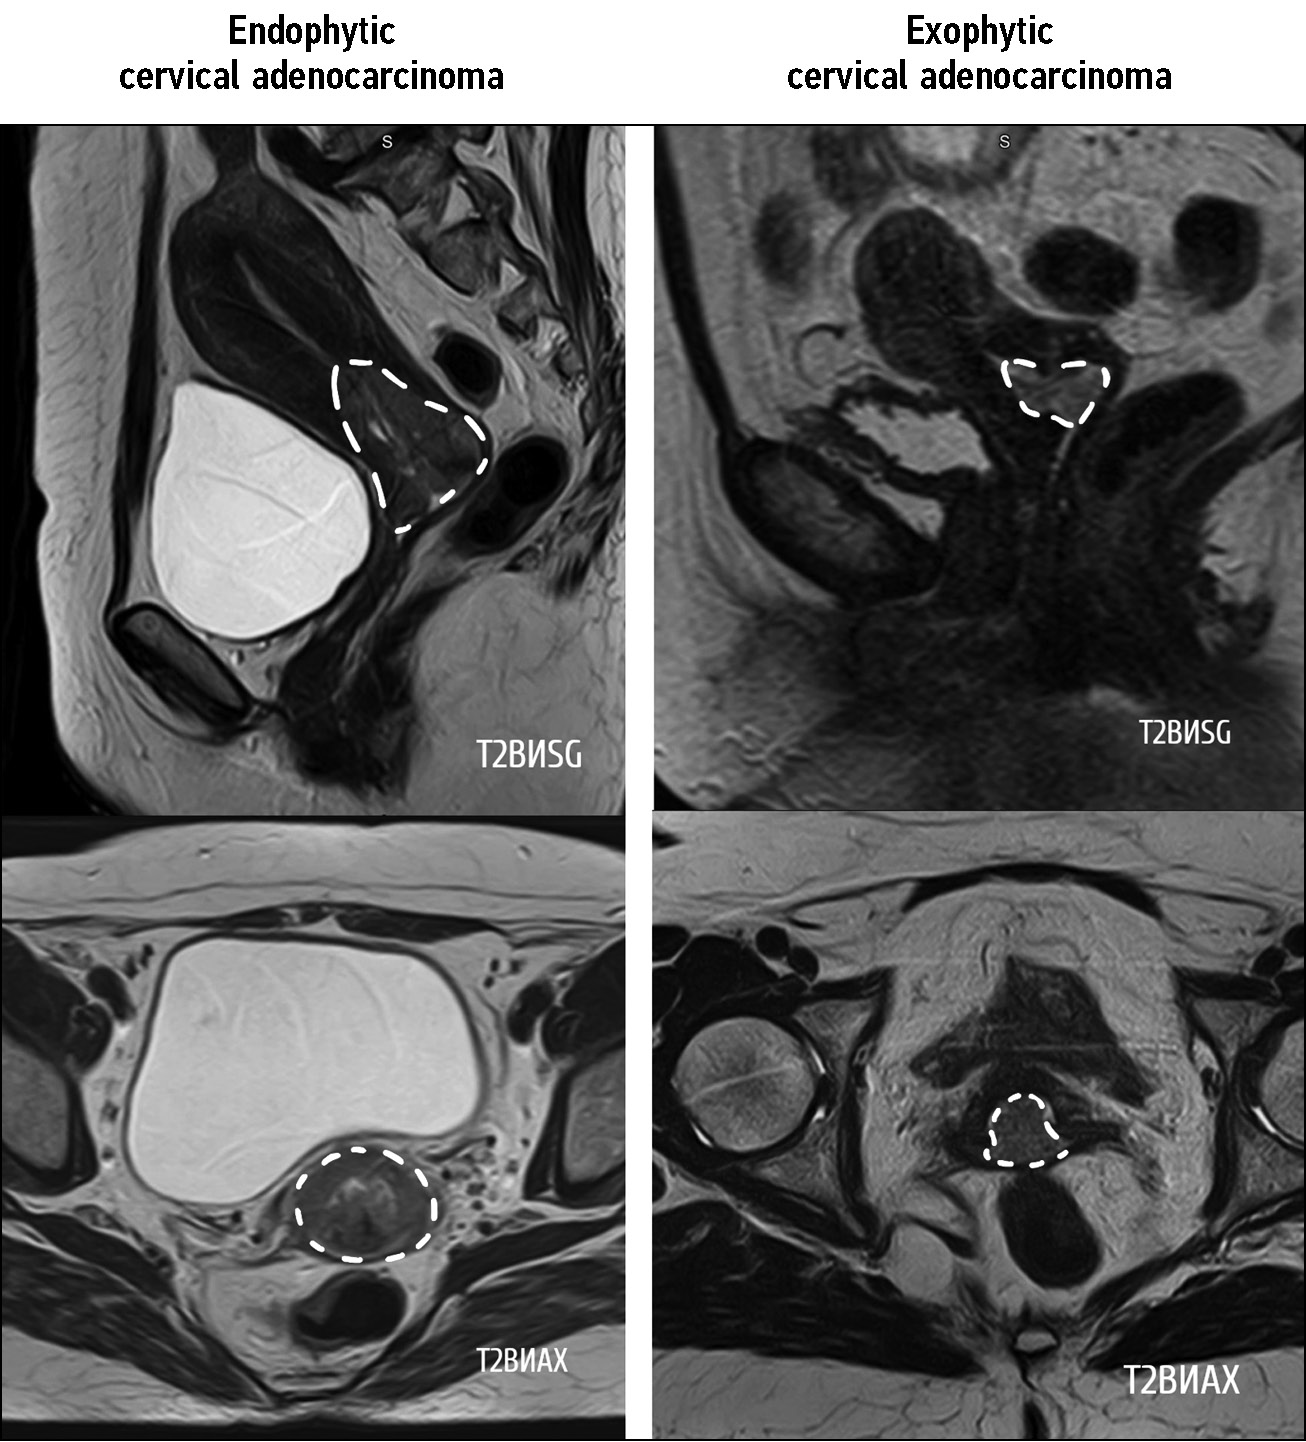

We identified two types of tumor growth in the cervical stroma: the most common were the endophytic type (75%, n = 15), characterized by diffuse enlargement and barrel-shaped cervical transformation (Fig. 3), and exophytic type, which occurred in 25% of cases in the present study (n = 5). Exophytic tumors were most commonly located in the vaginal cervix, with tumor masses prolapsing into the vagina or cervical canal lumen (Fig. 3). The exophytic tumor was represented by different histologic subtypes of CA:

- Poorly and moderately differentiated typical endocervical adenocarcinoma, 2 cases

- Poorly differentiated serous adenocarcinoma, 1 case

- Adenosquamous carcinoma, 1 case

- Endometrioid endocervical adenocarcinoma, 1 case

Fig. 3. Сervical adenocarcinoma growth pattern. The upper row of images is T2-weighted images in sagittal plane, the lower one — in axial plane.

Furthermore, endophytic tumors were characterized by different histologic types and differentiation patterns. No correlation was found for the type of tumor growth and its histologic subtype.